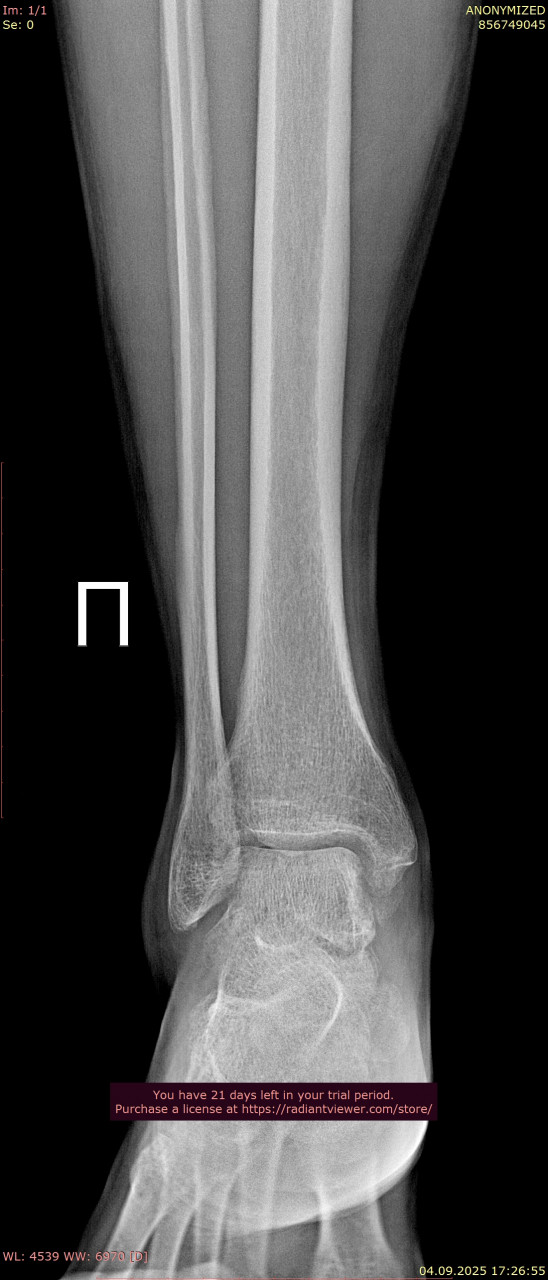

Посмотрите, пожалуйста, снимки голеностопного сустава от 23.06.2025, когда был перелом, и спустя почти 11 недель от 04.09.2025. Переломы срослись нормально? нужно ли делать еще один рентген в будущем? От 23.06.2025 прикрепляю только одну проекцию из за лимита сайта.

Здравствуйте. По вашим снимкам костная мозоль сформировалась, перелом срастается удовлетворительно, признаков смещения нет. Дополнительный рентген обычно не требуется, если нет боли или отёка, но окончательное решение принимает лечащий травматолог при очном осмотре.